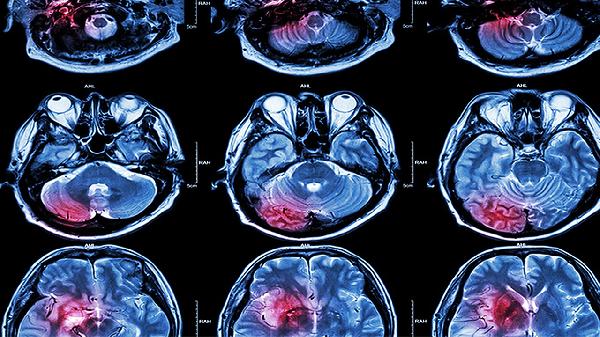

脑梗死患者除规范用药外,需保持低盐低脂饮食,每日钠盐摄入不超过5克,限制动物内脏和油炸食品。适当进行有氧运动如散步、太极拳,每周3-5次,每次30分钟。严格监测血压、血糖、血脂指标,戒烟限酒,保证充足睡眠。定期复查颈部血管超声和头颅影像学检查,出现肢体无力加重或言语不清需立即就医。